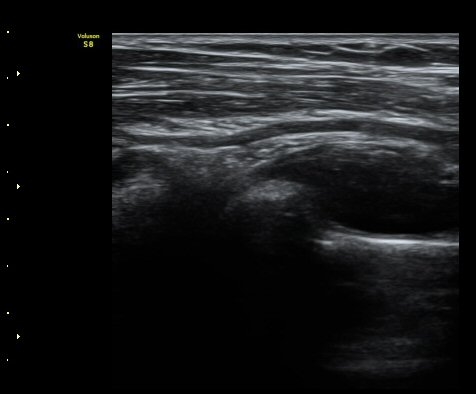

¼ÒµÎ Ⱦ´Ü¸é°Ë»ç¿¡¼­ ¿ä°ñ½Å°æ Èİñ°£½Å°æÀÌ Á¤»óÀûÀ¸·Î °í³ªÂûµÈ´Ù(±×¸² 1).